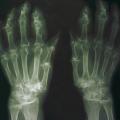

Les radiographies permettent de déceler des modifications ostéocartilagineuses asymétriques (mains, pieds, poignets, coudes, genoux), secondaires à la réaction inflammatoire autour des tophus, comportant :

• des érosions osseuses initiales caractéristiques : encoche épiphysaire (fig. 3) avec un éperon osseux (aspect en hallebarde) ;

• une image d’empreinte dans les parties molles (augmentation de la densité des parties molles dues au tophus) très évocatrice (fig. 4) ;

• un interligne longtemps conservé (contrairement aux autres rhumatismes destructeurs) [fig. 3] jusqu’au stade de goutte chronique et l’absence de raréfaction osseuse périarticulaire permettant de différencier la goutte d’autres arthropathies ; à un stade avancé, la goutte tophacée peut avoir un potentiel destructeur à la fois articulaire et osseux (fig. 4).